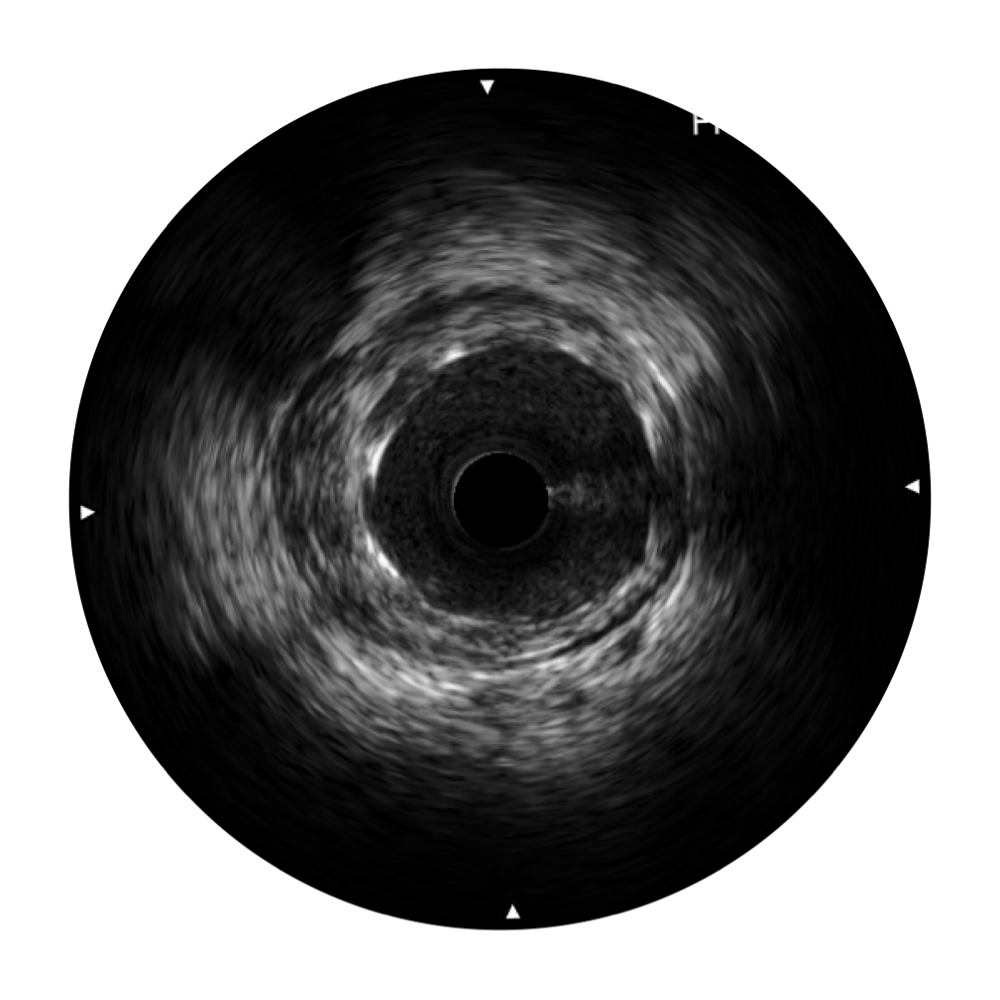

传统IVUS图像

对比传统IVUS导管成像,新葡的京集团8814检测站宽频IVUS图像的近场支架梁显影更细腻,远场中膜外血管仍清晰可辨,兼顾远中近,兼顾分辨力与穿透深度